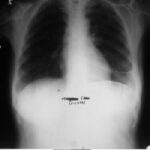

1991 Eylül - İlk Başvuru

Nefes darlığı, göğüs ağrısı - plevral sıvı

Ödem kayboldu, radyoloji normale yakın

Tetkiklerde sol plevra boşluğunda sıvı saptandı.

Torakoskopi ve Coparvacs uygulamasına rağmen akciğerde tam ekspansiyon sağlanamadı.

Radyolojik bulgular normale yakın hale gelmişti ve immünomodülatör tedaviyi kesmesi önerildi.